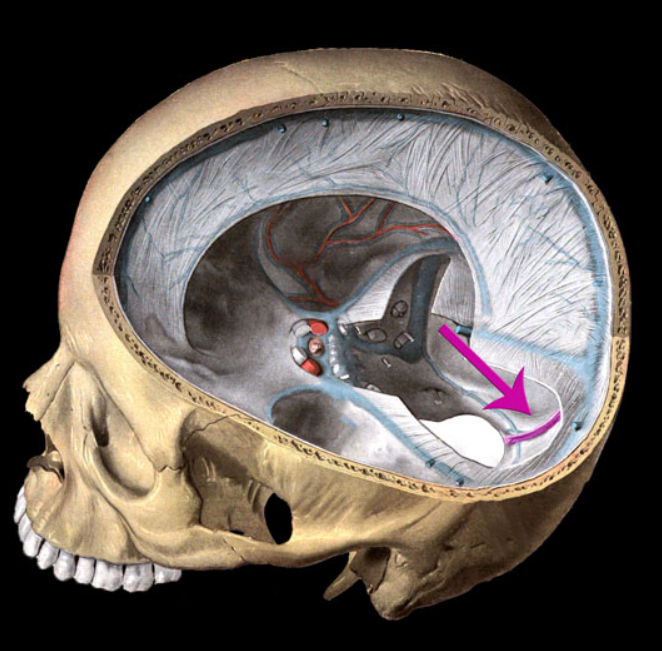

falx cerebri

tentorium cerebelli